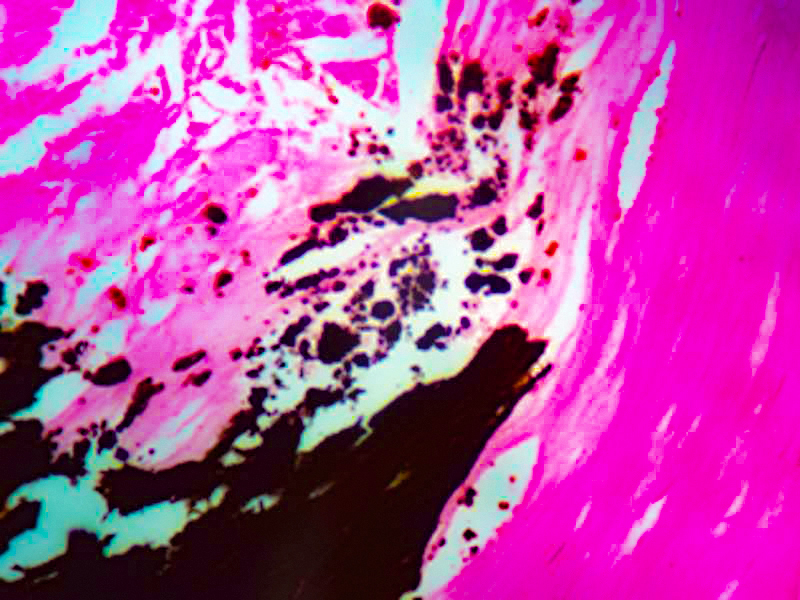

The Calcium Stain Kit (Modified Von Kossa) is intended for use in the histological visualization of calcium deposits in paraffin sections.